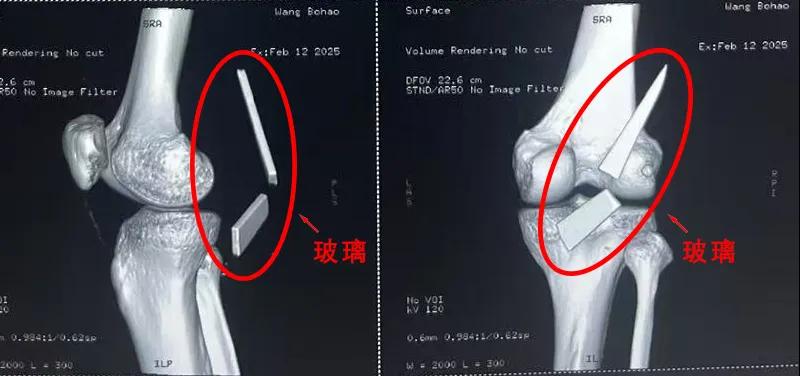

13厘米碎玻璃扎入腿中,漯河醫專二附院顯微外科緊急“拆彈”......

患者家屬這才開始意識到問題的嚴重性,便帶著孩子到鄉鎮衛生院檢查——結果顯示右膝關節后方竟然殘留著兩塊兒鋒利的碎玻璃,測量后預估玻璃總長將近13厘米!

由于玻璃位置毗鄰坐骨神經和股動脈,一旦刺破股動脈,將嚴重威脅生命。家屬著急萬分,想著能否盡快手術取出碎片,于是慕名來到漯河醫專二附院(漯河市骨科醫院、漯河市立醫院)手顯微外科(修復重建骨感染科)。

術中,馬廣輝醫生憑借扎實的理論知識和嫻熟的顯微外科技術,順利找到深深刺進肌肉的兩塊玻璃,肉眼可見玻璃尖端距股動脈僅有不到半公分的距離!如果患者再耽誤半天或者再多活動幾次膝關節,小指粗的股動脈很有可能被玻璃扎破,后果難以想象。

最終,馬廣輝醫生在血管、神經表面順利取出兩塊玻璃碎片,拆除了埋在患者膝關節的“炸彈”。在告知患者家屬術中情況后,家屬懸著的心終于放了下來。